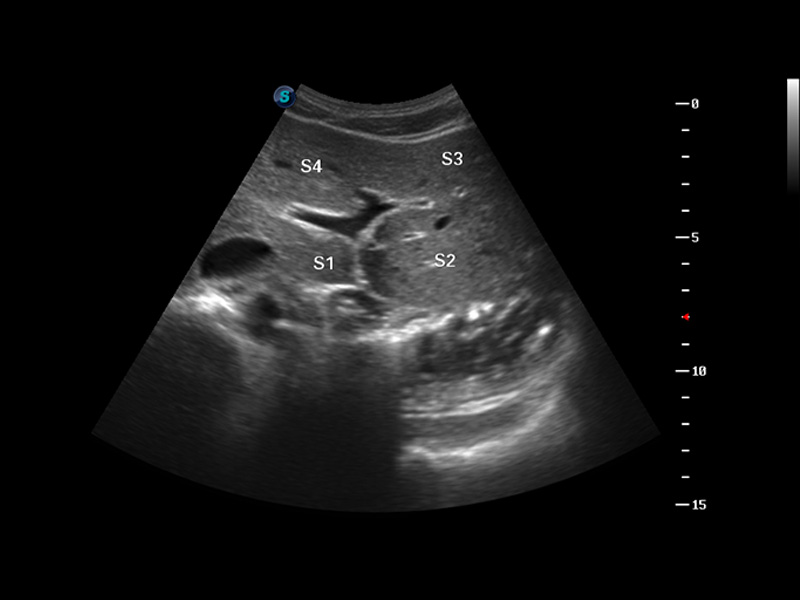

S8 EXP便携式彩色多普勒超声诊断仪是米兰官方网站研发的高端全身应用型便携彩超。高通道的VIS平台融合可视化(Visual)、智能化(Intelligent)和人性化(Smart)的特点,配以米兰官方网站自主研发生产的探头大家族,使您能够快速、准确的获得病人信息,提高工作效率的同时减轻疲劳。

谐波成像